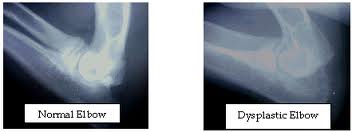

Elbow dysplasia is a general term used to identify an inherited polygenic disease in the elbow of dogs. Three specific etiologies make up this disease and they can occur independently or in conjunction with one another. These etiologies include:

-X-rays are used to evaluate the condition of joint surfaces